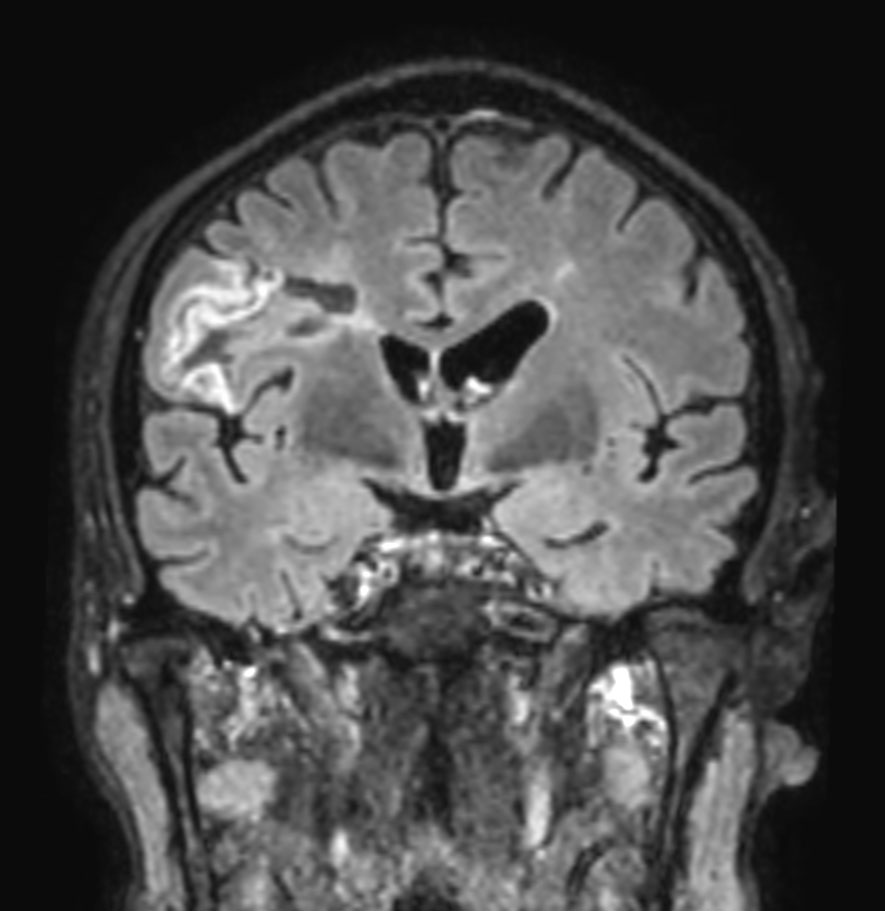

Patient with multiple brain lesions. The ExamCard includes Compressed SENSE to accelerate the entire exam and techniques for motion reduced imaging (MultiVane XD), 3D imaging to acquire high resolution data in multiple directions, 3D susceptibility weighted imaging (SWIp), DWI with EPIC Brain to bring down any residual distortion and Computed DWI to generate synthetic high b-value images.

3D T2w FLAIR Compressed SENSE

3D T2w FLAIR (reformat) Compressed SENSE